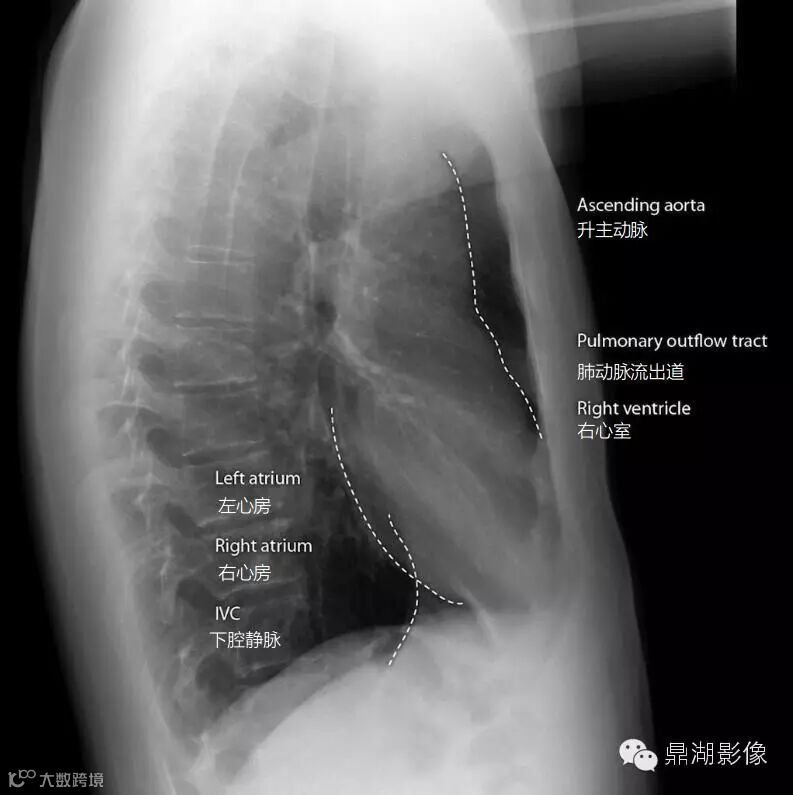

心纵膈的外轮廓线